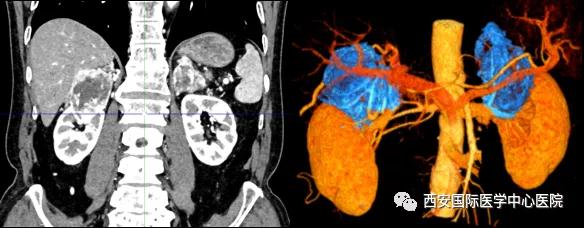

今年七十五歲的患者,來自陜西省商洛市,四月前因腰背部疼痛就診于當(dāng)?shù)蒯t(yī)院,行CT檢查發(fā)現(xiàn)“右腎、雙側(cè)腎上腺占位,前縱膈淋巴結(jié)腫大,雙肺多發(fā)結(jié)節(jié)、胸椎骨質(zhì)破壞,考慮轉(zhuǎn)移瘤”。為進一步診斷治療,患者的兒子帶他來到西安某三甲醫(yī)院,查泌尿系CT提示“右腎占位性病變,多考慮腎癌,雙側(cè)腎上腺多發(fā)轉(zhuǎn)移灶,腹膜后多發(fā)腫大淋巴結(jié)”;行穿刺活檢提示“腎透明細胞癌”;并給予患者口服靶向藥物的治療方案。

自四月份至今,患者一直口服靶向藥物治療(阿昔替尼5mg 2次/日),期間無不良反應(yīng),目前腰背部疼痛癥狀也有所緩解,復(fù)查影像學(xué)資料提示瘤體較前縮小,腫瘤完整切除的可能性明顯提高;而且患者的兒子也是一名外科醫(yī)生,所以他更想為父親完成后續(xù)的手術(shù)治療。

患者一家慕名前來到西安國際醫(yī)學(xué)中心醫(yī)院找到楊增悅教授。楊增悅教授仔細看完患者的之前的影像學(xué)及病理資料后,診斷為:右腎透明細胞癌(T4N1M1);并安排他住院。而后,主管醫(yī)生及時為他完善了術(shù)前檢查及評估。7月15日,在麻醉手術(shù)中心柴偉主任、王彬榮副主任、李娟護士長、李瑞剛護士長及全體麻醉手術(shù)中心團隊的有力保障下,成功完成了這臺“大”手術(shù)。

手術(shù)由楊增悅教授主持,舒濤主治醫(yī)師、王東主治醫(yī)師主刀,黃怡醫(yī)師、王平醫(yī)師協(xié)助完成。由于第四代達芬奇機器人更加靈活和精準(zhǔn)的特性,手術(shù)全程順利,尤其是完全精準(zhǔn)的“解鎖”了右腎動脈和右腎靜脈的數(shù)十根交互纏繞的分支血管。術(shù)后患者麻醉恢復(fù)后生命體征平穩(wěn),順利返回泌尿外科普通病區(qū)進一步康復(fù)。